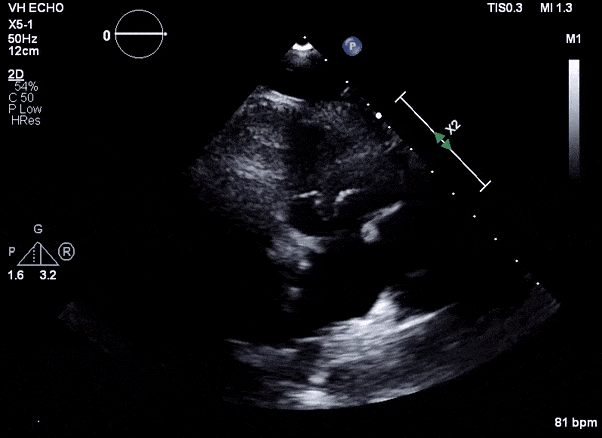

Case 3

Role of Echocardiography

- Echo plays an important role in the diagnosis of infective endocarditis.

- Helps identify vegetations, new valvular lesions, abscess, and other complications of endocarditis.